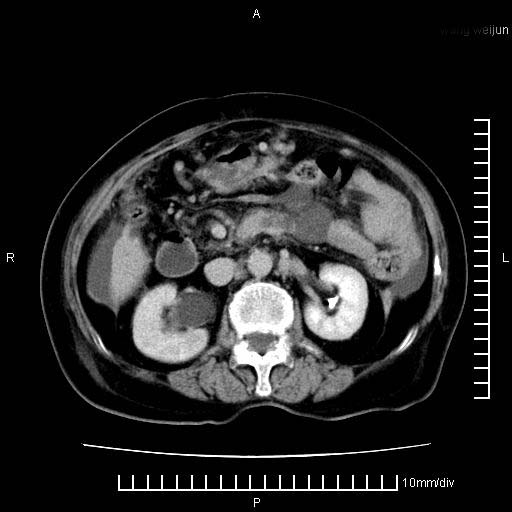

标题: CT28280:腹部增强:女性,80岁

上腹疼痛月余,外院核磁诊断胰腺癌。现临床示右下腹可明显触及包块,可片子上怎么没有看到?

1.胰腺颈体部癌。

2。腹腔积液。

3。右胸腔积液,伴右肺下叶部分萎陷。

4。右肾盂囊肿。

胰腺体部癌累及周围器官,腹膜、粘连

1。胰腺ca伴腹膜腔转移

2。肝左叶低密度灶,考虑转移可能

胰腺体部癌累及周围器官,腹膜、粘连,临床摸到的可能是粘的组织

胰腺结构模糊,胰尾部见囊性包块,周围脂肪密度增高,左肾前筋膜增厚,胸水、腹水。不符合胰腺ca伴腹膜腔转移。考虑胰腺炎伴假性囊肿形成、胸腹腔积液。

右肾盂囊肿。

1)考虑胰腺癌并胰腺假性囊肿形成。2)肝内低密度灶,不排除转移。3)右肾盂积水。4)腹水。5)右侧胸腔积液并右肺下叶部分膨胀不全。